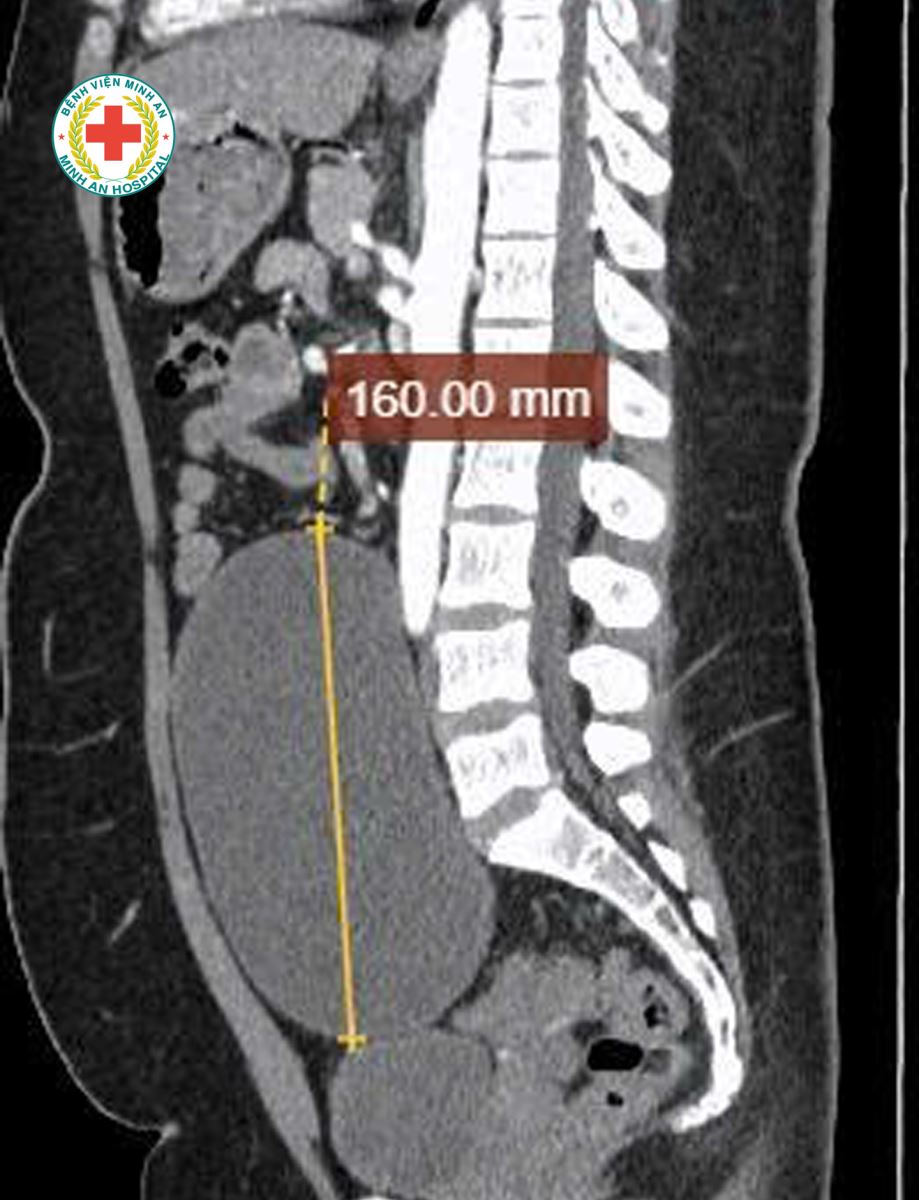

Khoa Sản – BVĐK Minh An vừa tiếp nhận tiếp nhận một trường hợp đặc biệt: U nang buồng trứng kích thước rất lớn, tương đương thai khoảng 20 tuần tuổi, người bệnh gần như không có triệu chứng rõ ràng, chỉ xuất hiện ra máu bất thường ngoài chu kỳ. Điều đáng chú ý là bênh nhân mới 22t, chưa từng sinh nở.